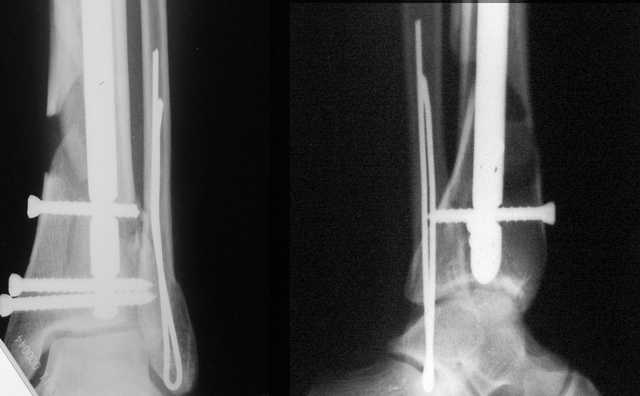

АЧ>если сопоставить стоимость отечественного гвоздика и пластины Synthes

Для значительной категории наших больных операции с применением имплантов SYNTHES и MATHYS - бесплатны, при производсвенной травме оплачивает ФСС, быт. травма,автодорожка при наличии полиса ДМС, разным льготникам часть ФОМС, а часть ад. города, причём для этих категорий АО - стандарт.

При штифтовании ортопедическим столом не пользуйтесь?